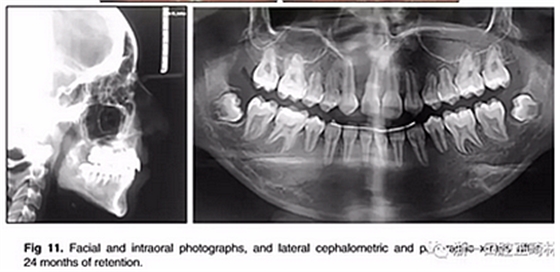

經(jīng)過24個(gè)月的保持后,咬合保持得很好(圖11 ; 圖12)。在上牙弓中,應(yīng)用固定舌側(cè)保持器以防止任何復(fù)發(fā)傾向。在下牙弓中,治療后拔除第三磨牙。